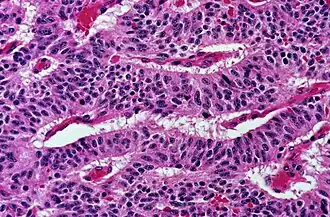

Trabecular, elongated (rod-shaped) groups of cells. -